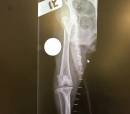

It is hard to believe but Rufus is finally well enough to travel to his new home in Brewster, NY.  It has taken almost three months to get him well enough because he had such terrible breaks in his legs.  The good news is that he can run and play to his hearts content.   Rufus finally has his Special Home and has been Adopted.